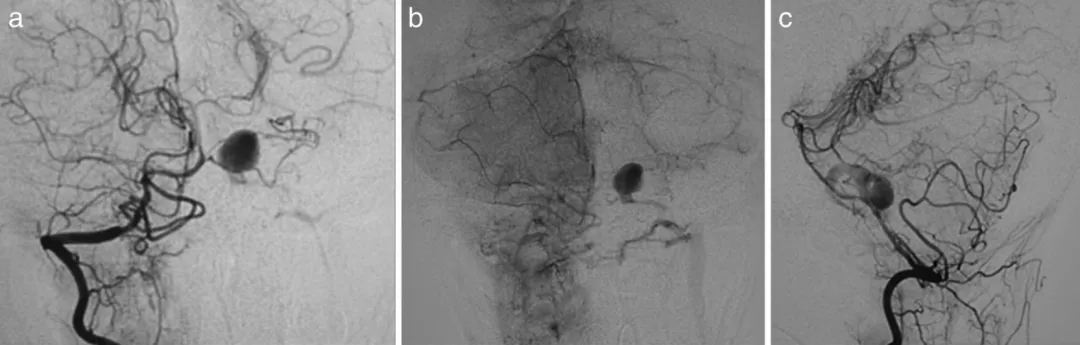

更棘手的是,入院第7天的血管造影证实,这个动脉瘤不仅是创伤后形成的,还合并了动静脉瘘——一条异常静脉直接从动脉瘤瘤顶引流至颈内静脉,相当于血管系统出现了“短路”。

图a,b,c为第7天的右椎动脉造影。动脉瘤位于左AICA的近端。

更危险的是,14天后复查造影,动脉瘤已经明显增大,随时可能破裂大出血。

图d,e为第14天右椎动脉造影。动脉瘤扩大,房室瘘更加明显。